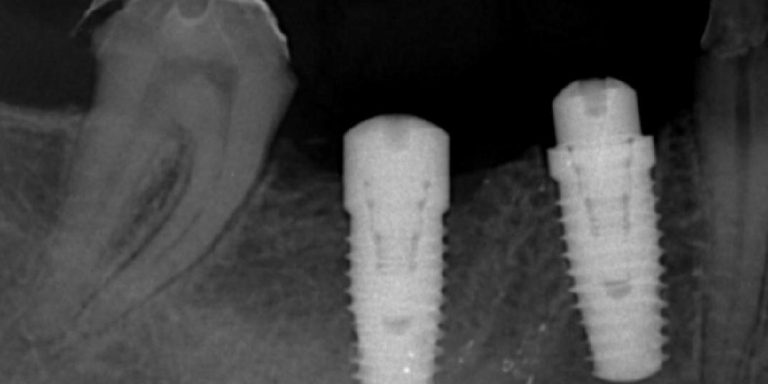

วางแผนด้วยเอกซเรย์ 3 มิติ เพื่อความแม่นยำ และปลอดภัย ในการปลูกรากเทียม ออกแบบวางแผนการรักษาด้วยระบบ Digital